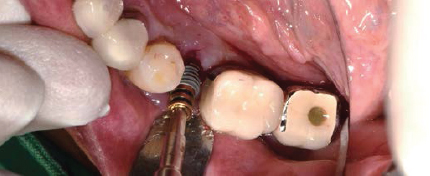

Volume Up Gauge로 직경 확인 (Ø8.5)

-

Volume Up Gauge홈에 맞춰 Point Drill 위치

Point Drill 후 생성된 구멍에 Ø8.5 Volume Up Parallel Pin을 끼움

이 후, 앞의 임플란트 위치에 맞춰 Volume Up Gauge 위치 시켜 직경확인 (Ø7.5)

Volume Up Gauge 홈에 맞춰 Point Drill 위치

Point Drill 후 생성된 구멍에 Ø7.5 Volume Up Parallel Pin을 끼움

제조사의 식립 순서에 맞춰 Drilling 후 Fixture 식립

Fixture에 Volume Up Healing Abutment 체결